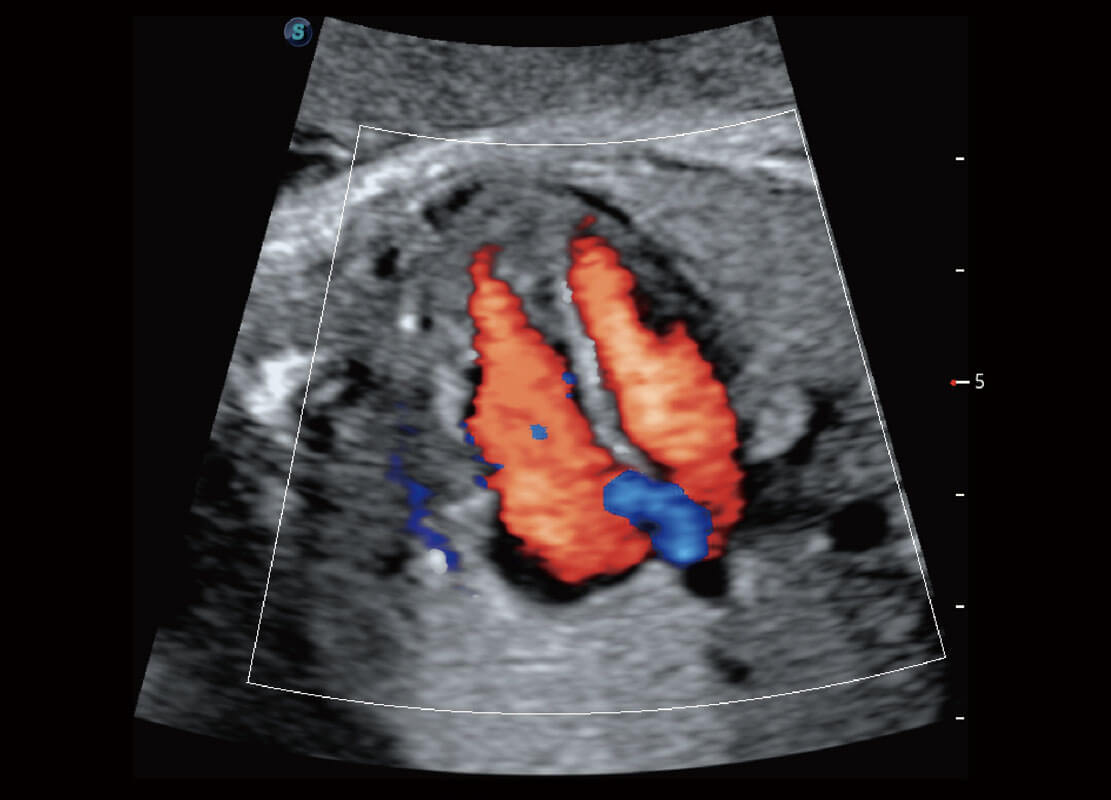

四腔切面

四腔心血流